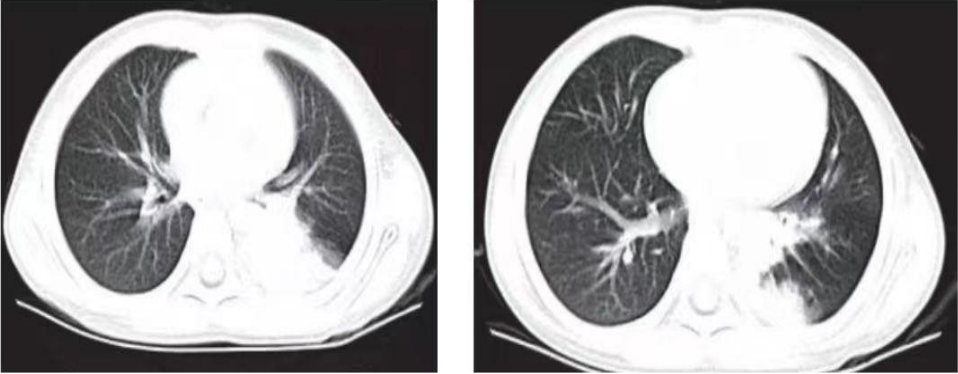

图片

腺病毒肺炎,表现为类似大叶性肺炎征象